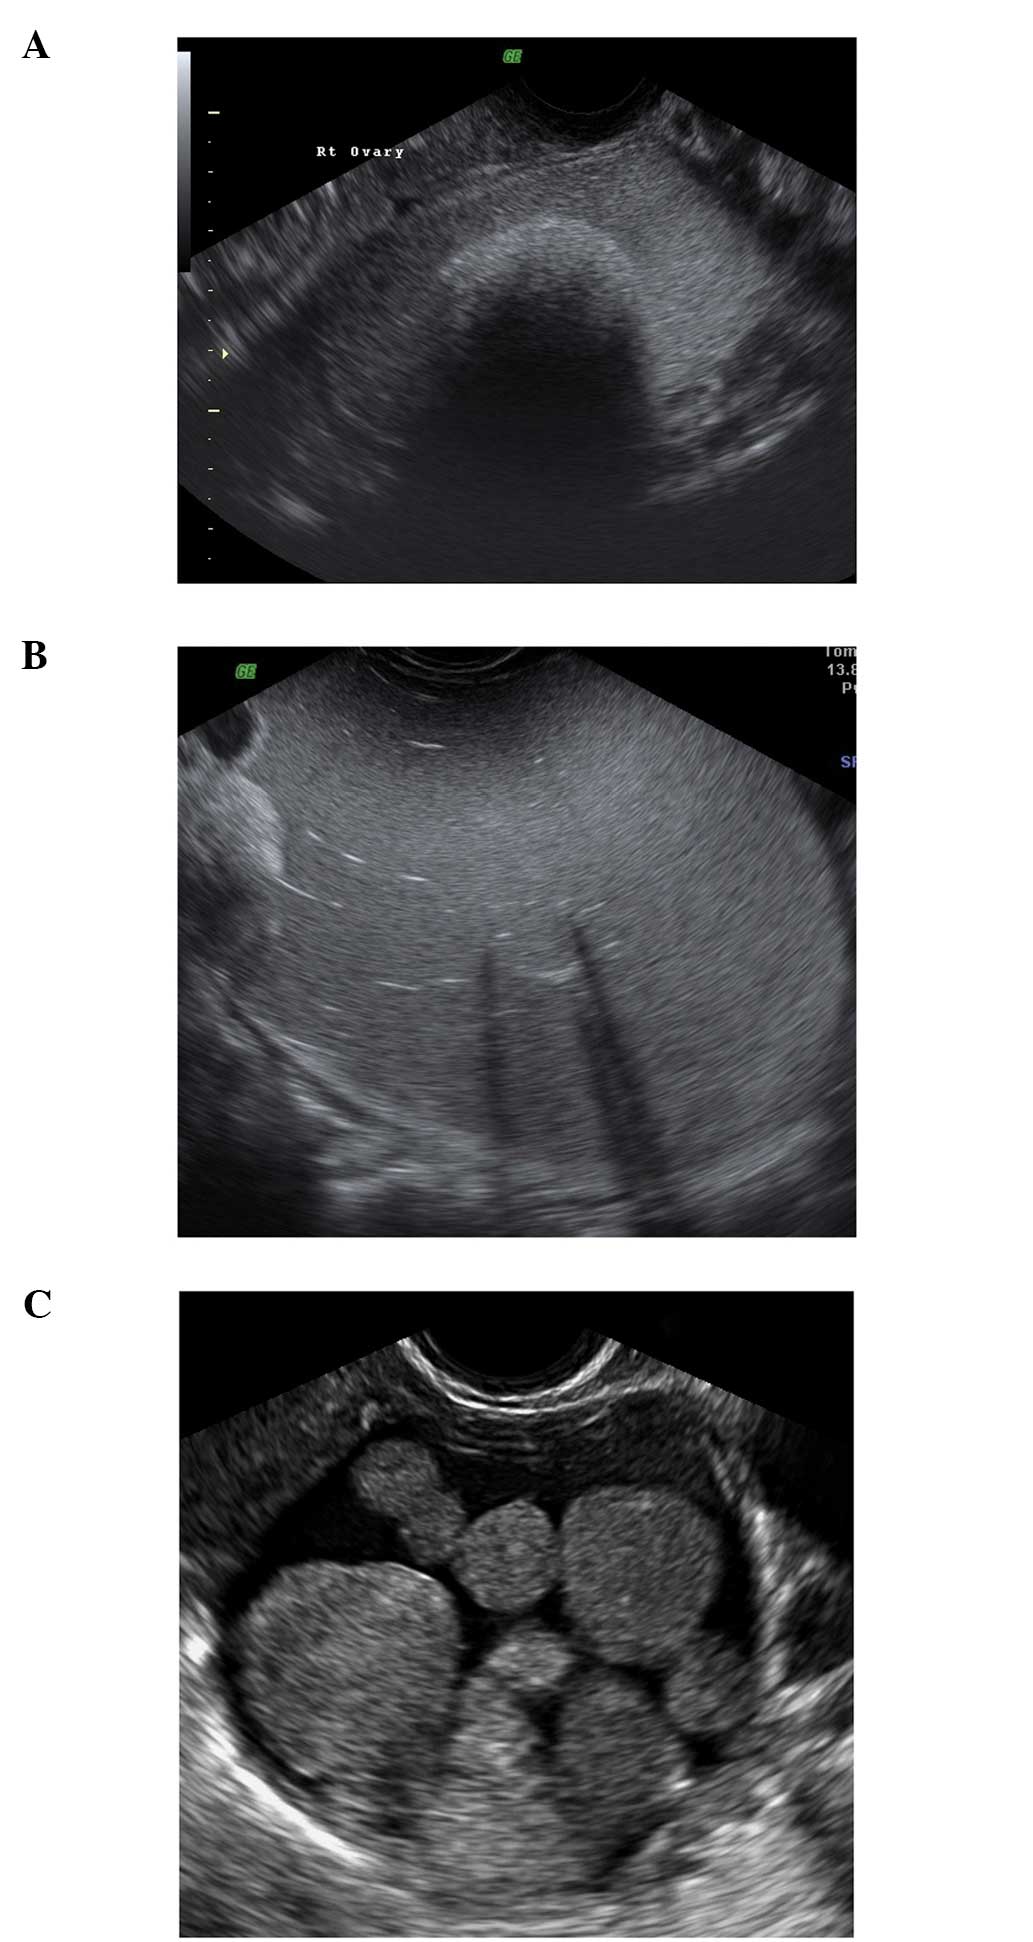

A tubo-ovarian complex represents the involvement of ovarian tissue in the inflammatory process. Normal ovarian parenchyma is visible, but it is usually seen separate from tubal structures (15,22–24) (Fig. 9).

Figure 9

A tubo-ovarian complex. (A) Ultrasound appearances. (B) The same case at laparoscopy.

In a tubo-ovarian abscess, ovarian tissue is no longer visible; the lesion may be unilocular, solid or multilocular-solid with mixed or ground-glass echogenicity. On the basis of the ultrasound features, these have to be differentiated from endometriomas or hemorrhagic cysts (15,22–24). In practice the clinical features associated with an abscess make the diagnosis relatively straightforward.